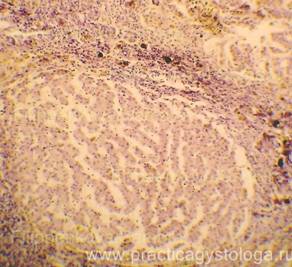

Рис. 1-4. Метастазы аденокарциномы молочной железы в толще эпикарда и субэпикардиально в миокарде с полным его замещением. Труп женщины, 57 лет. Окраска: гематоксилин-эозин. Увеличение х100. Стеклопрепарат предоставлен врачом - судебно-медицинским экспертом судебно-гистологического отделения ГУЗ «Самарское ОБСМЭ» Ким С.В.